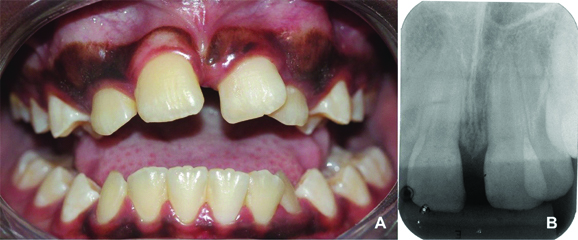

Extraoral clinical examination revealed the presence of oedema in the region between the nose wing and upper lip on the right side of the face, causing slight facial asymmetry [Table/Fig-1a]. The intra-oral examination revealed that the patient had mixed dentition and was caries free [Table/Fig-1b]. He had unsatisfactory oral hygiene, with biofilm on all teeth. A normal overbite and overjet, presence of midline deviation, eruption of tooth 21 in gyroversion, crossbite of teeth 21 and 22 and crowding were verified. The presence of a painless increased volume of hard consistency in the region of the upper central right incisor and the prolonged retention of the primary upper central incisors were observed [Table/Fig-1c].

a) Extraoral view showing slight facial oedema on the right side of the face and asymmetry. b) Intraoral occlusal upper photography showing the prolonged retention of the primary upper central incisors and the tooth 21 in gyroversion. c) Frontal view showing midline deviation and crossbite of teeth 21 and 22.

a) Intraoral frontal view and b) periapical radiography after 18 months of follow-up.